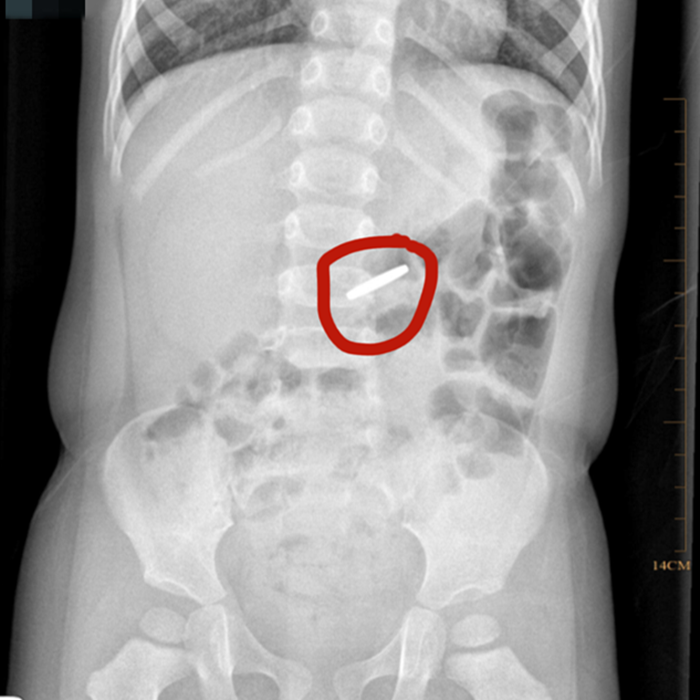

溫附二兒科消化專家胡偉國(guó)主任醫(yī)師會(huì)診后,立即為小京京開具X光片檢查,發(fā)現(xiàn)異物滯留于胃部,考慮到硬幣長(zhǎng)時(shí)間在胃內(nèi)可能引起胃黏膜損傷,胡偉國(guó)馬上聯(lián)系麻醉科、內(nèi)鏡中心,在靜脈麻醉下為小京京行內(nèi)鏡下胃內(nèi)異物取出術(shù)。

術(shù)中發(fā)現(xiàn)硬幣果然還在胃里,好在胃黏膜無受損,胡偉國(guó)主任通過專用異物鉗很快將硬幣取出。該硬幣直徑約19毫米,已被胃液略微腐蝕。